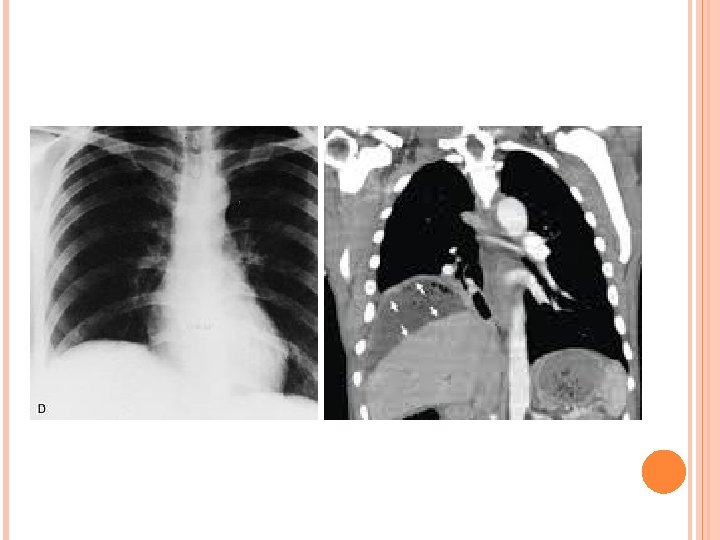

INVESTIGATIONS • Blood tests usually show a leucocytosis and raised C-reactive protein. • A plain radiograph sometimes demonstrates the presence of gas or a pleural effusion. On screening, the diaphragm is often seen to be elevated (so called ‘tented’ diaphragm. • Ultrasound or CT scanning is the investigation of choice and permits early detection of subphrenic collections. • Radiolabelled white cell scanning may occasionally prove helpful when other imaging techniques have failed.